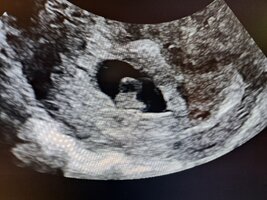

OijoiMeillÀ oli hati aamulla klo8.15 ja sen jÀlkeen onkin pÀivÀ menny aika sumussa. Ultrassa paljastui siis kaksi ja koska meille on siirretty 1kpl 4pv ikÀinen blasto niin identtiset kaksoset siis tulossa. JÀrkytys oli melkoinen vaikka vahva intuitio sanoi, ettÀ nyt ei ole kaikki "normaalisti" ja siks varasinkin ton ylimÀÀrÀsen ultran. Kohdusta löytyi myös aktiivista vuotoa, jonka toivotaan loppuvan eikÀ aiheuttas mitÀÀn pahempaa, mutta sitÀ vuotoakin nyt sit vielÀ jÀnnÀtÀÀn.

Juhannuksen jÀlkeen sit seuraava ultra ja toivotaan, ettÀ molemmat pysyisi matkassa. Vahva syke oli molemmilla+